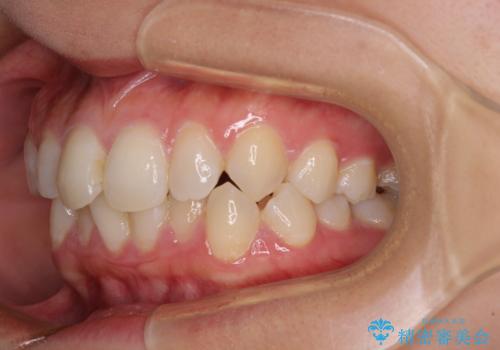

- 前歯のデコボコと歯肉に埋もれている奥歯を気にして来院された患者様です。

インビザラインでの治療を希望されていましたが、左右の下顎大臼歯が歯肉に埋もれており、特に右側は歯軸が顕著に傾斜していたため、インビザライン単独での治療は困難と判断し、ワイヤー装置を併用することとしました。

ワイヤー装置での下顎臼歯改善には時間がかかることが予想されたため、下顎のワイヤー矯正と並行して上顎をインビザラインで整え、その後インビザラインにより上下歯列を整える矯正治療を行うこととしました。